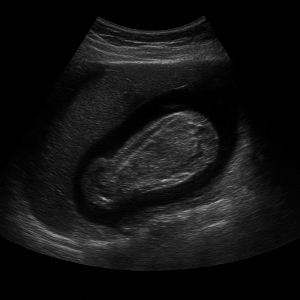

방광과 전립선(남성) 또는 자궁·난소(여성)

- 남성은 전립선 상태나 비대, 염증, 혹은 종양 여부를 확인할 수 있어요.

- 여성의 경우 자궁이나 난소 상태를 살펴보며, 난소 낭종, 자궁 근종, 혹은 다른 병변 의심도 파악할 수 있답니다.

또한 방광 상태, 예를 들어 잔뇨나 방광벽 상태도 초음파로 확인 가능해요.